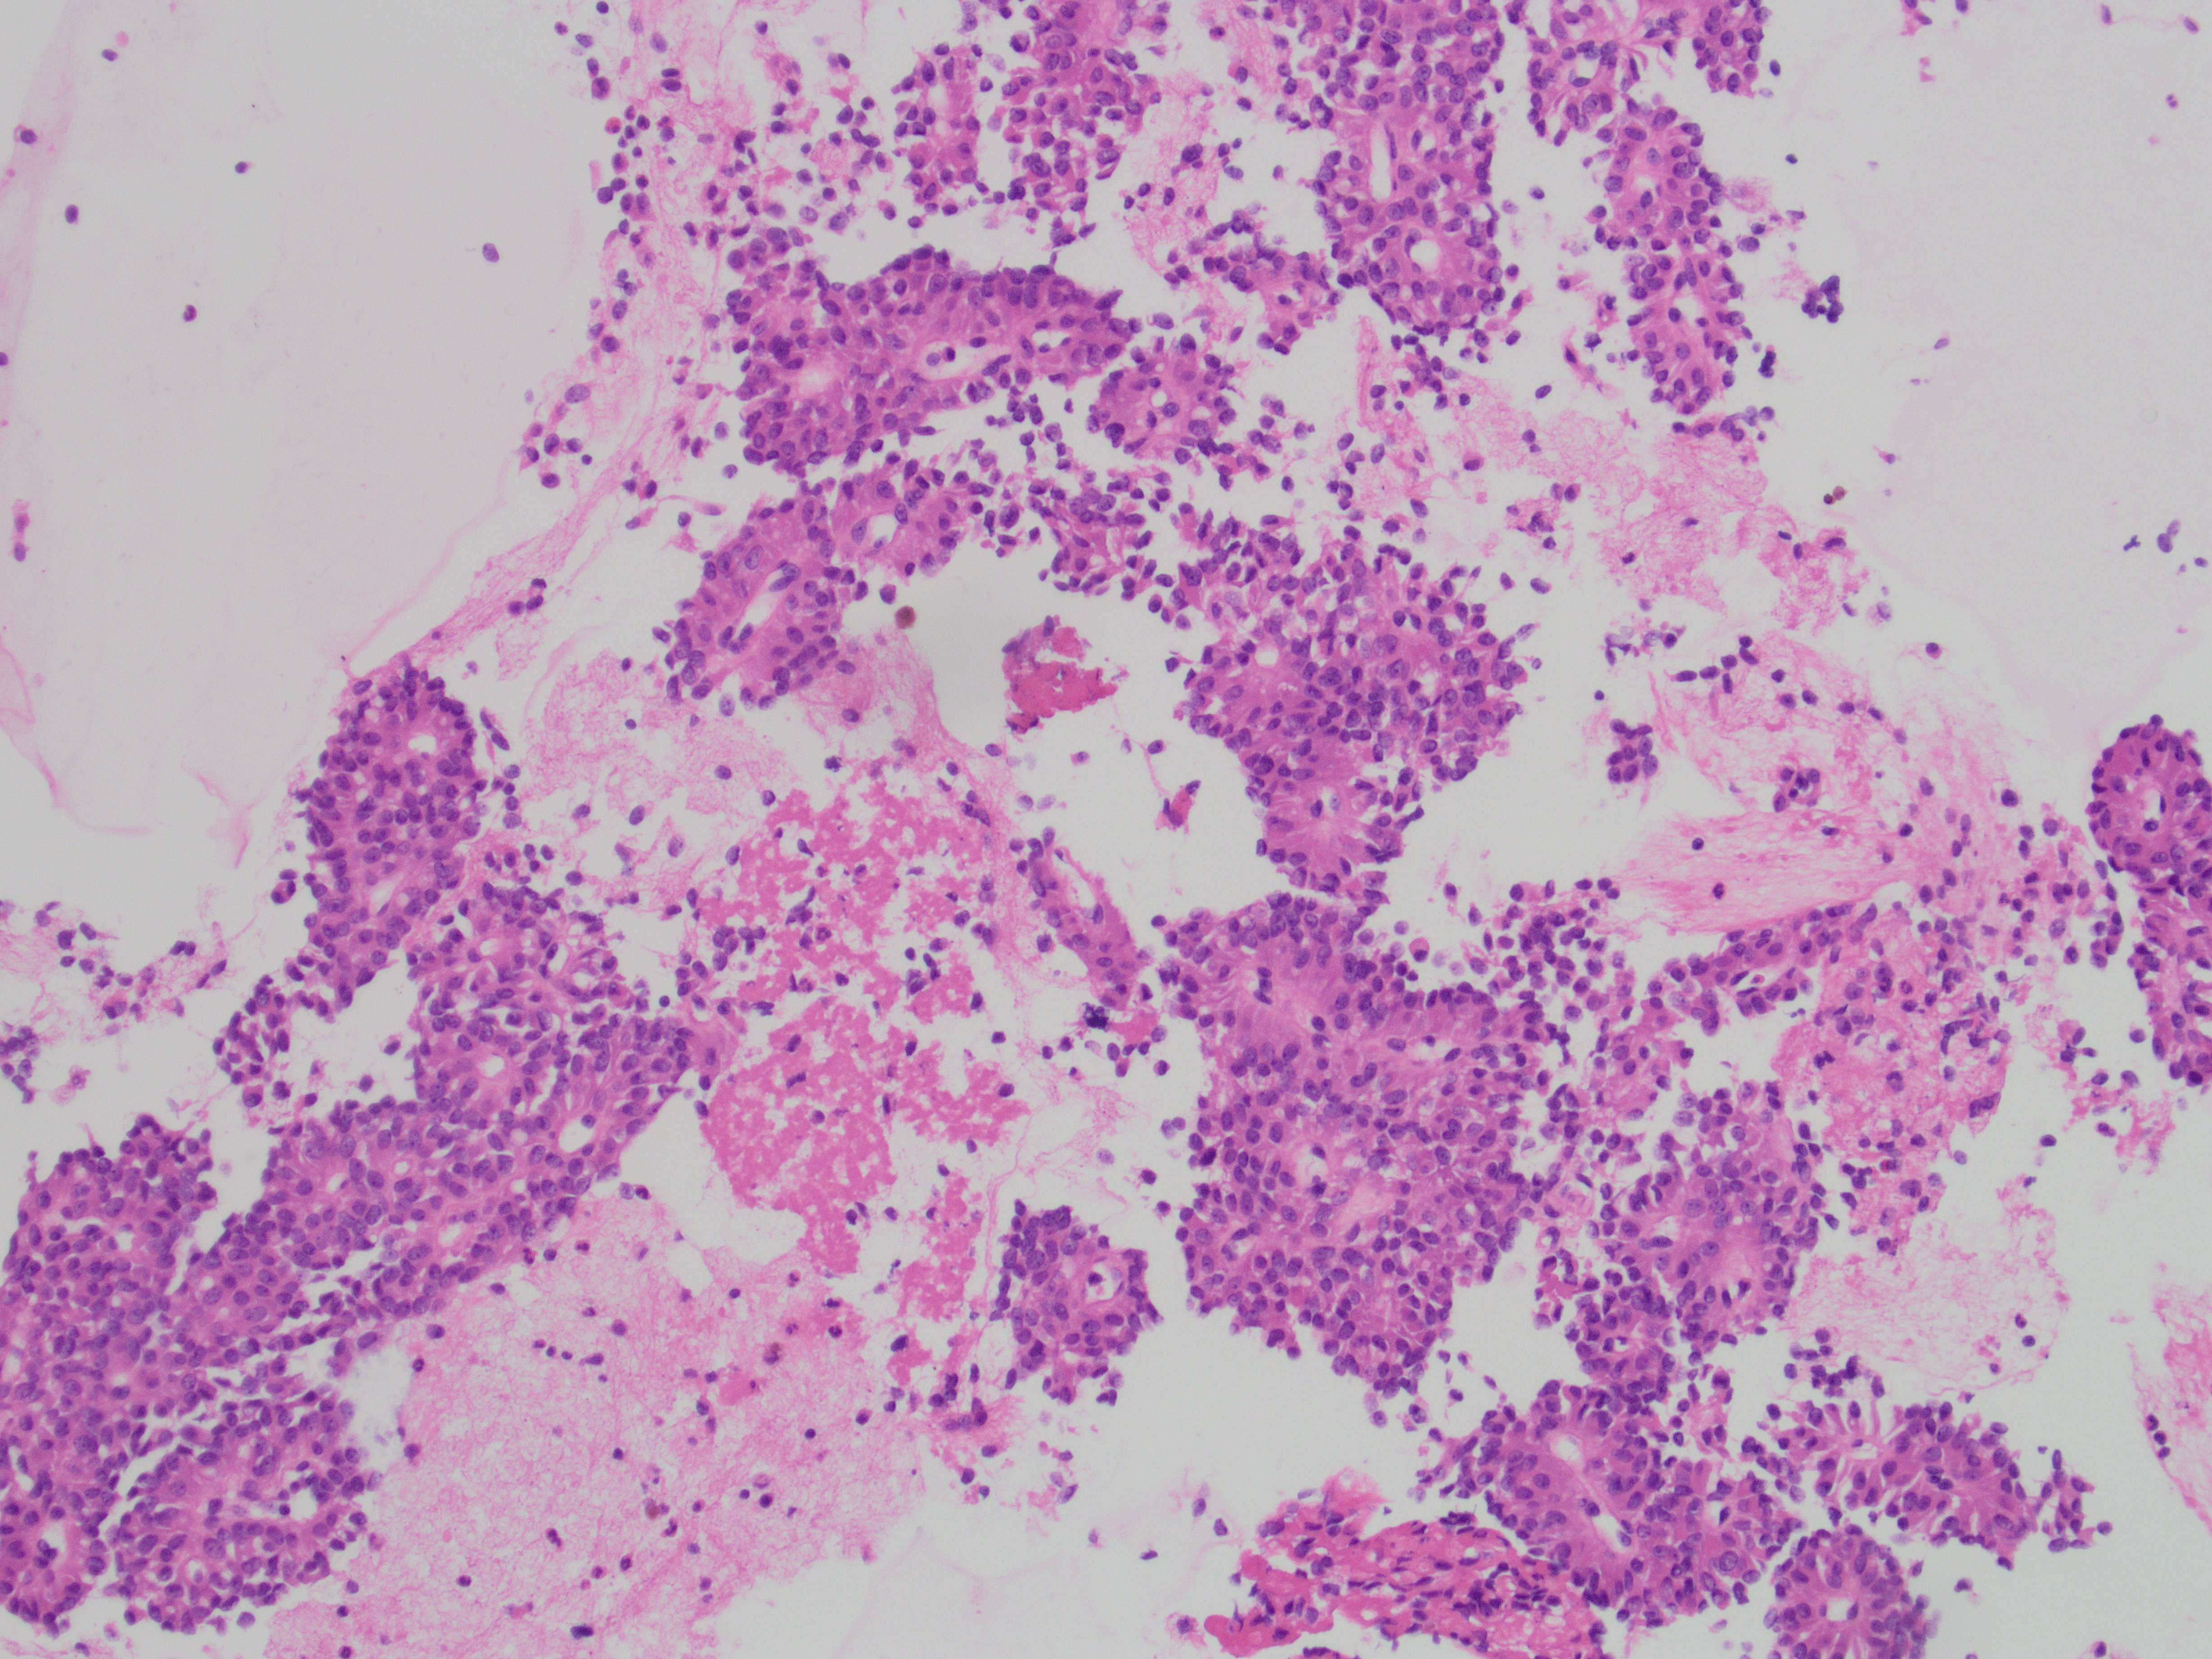

The specimen is richly cellular and consists of abundant monomorphic cuboidal nonmucinous cells, which are arranged as loosely cohesive groups and isolated cells (Figure 1). The neoplastic cells show delicate vacuolated cytoplasm with indistinct cell borders (Figure 2). These solid nests of loosely cohesive cells forming a cuff surrounding blood vessels result in a pseudopapillary architecture, which are well appreciated in the smear and cell block (Figure 3 and 4).

The differential diagnoses include pancreatic neuroendocrine tumor, solid pseudopapillary neoplasm and acinar cell carcinoma. By immunocytochemistry, the neoplastic cells show diffuse nuclear positivity for beta-catenin (Figure 5) and membranous positivity for CD10 (Figure 6). Also, the tumor cells are focally and weakly positive for synaptophysin (Figure 7). Taken together, the final diagnosis is solid-pseudopapillary neoplasm.